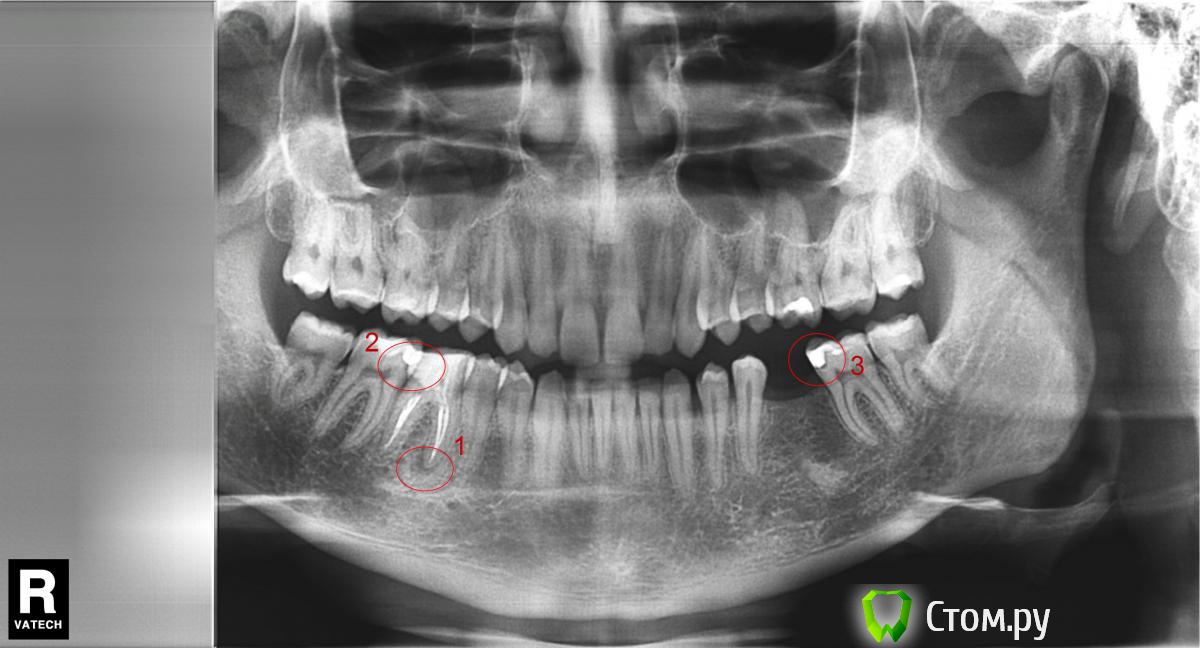

bobrdobr Опубликовано 5 февраля, 2014 Поделиться Опубликовано 5 февраля, 2014 Добрый вечер, Для планирования имплантации сделал панорамный снимок. Появилось несколько вопросов по терапии. В области 1 - это периодонтит? Зуб не беспокоит, был депульпирован и запломбирован два года назад. Нужно ли срочно перелечивать канал? В областях 2 и 3 темные кромки между пломбой и зубом могут быть кариесом? Понимаю, что панорамный снимок - не лучший способ диагностики. Заранее спасибо! Ссылка на комментарий

DmitrySH Опубликовано 6 февраля, 2014 Поделиться Опубликовано 6 февраля, 2014 Добрый вечер,1 - да, нужно. Хотя по снимку запломбировано нормально. 2 - возможно, но нужен визуальный осмотр Ссылка на комментарий

bobrdobr Опубликовано 21 февраля, 2014 Автор Поделиться Опубликовано 21 февраля, 2014 Спасибо всем за комментарии. Сегодня был у терапевта, все подтвердилось. 1. Полость на 27 зубе оказалась кариесом2. В областях 2 и 3 на снимке кариес Ссылка на комментарий